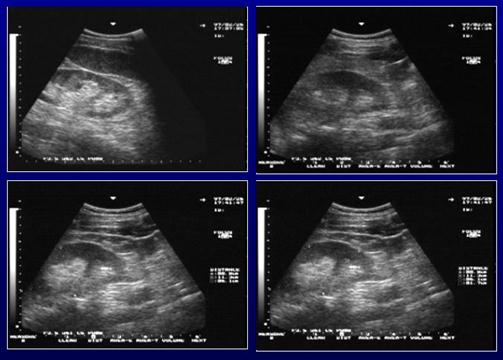

Рис. 17. УЗИ почек

Ультразвуковое исследование почек (УЗИ почек) – это малоинвазивная процедура, с помощью которой можно установить форму, размер и местоположение почек. Методика ультразвукового исследования почек позволяет быстро визуализировать почки, оценить их структуру. С помощью ультразвука почек можно оценить почечный кровоток.